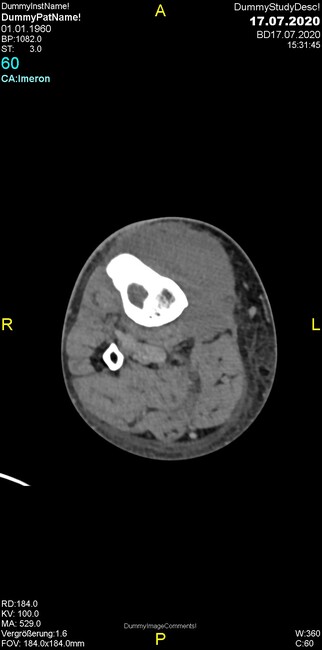

Um welche Modalitäten handelt es sich?

- Röntgen p.a. und lateral, CT coronar Knochenfenster, CT axial Weichgewebsfenster

Was fällt in der Projektionsradiographie auf?

Was fällt in der CT im Knochenfenster auf?

- Osteolyse der Tibiametaphyse unter Beteiligung der Kortikalis

Was kommt differentialdiagnostisch in Frage?

- Osteomyelitis mit Weichgewebsanteil

- Metastase mit pathologischer Fraktur